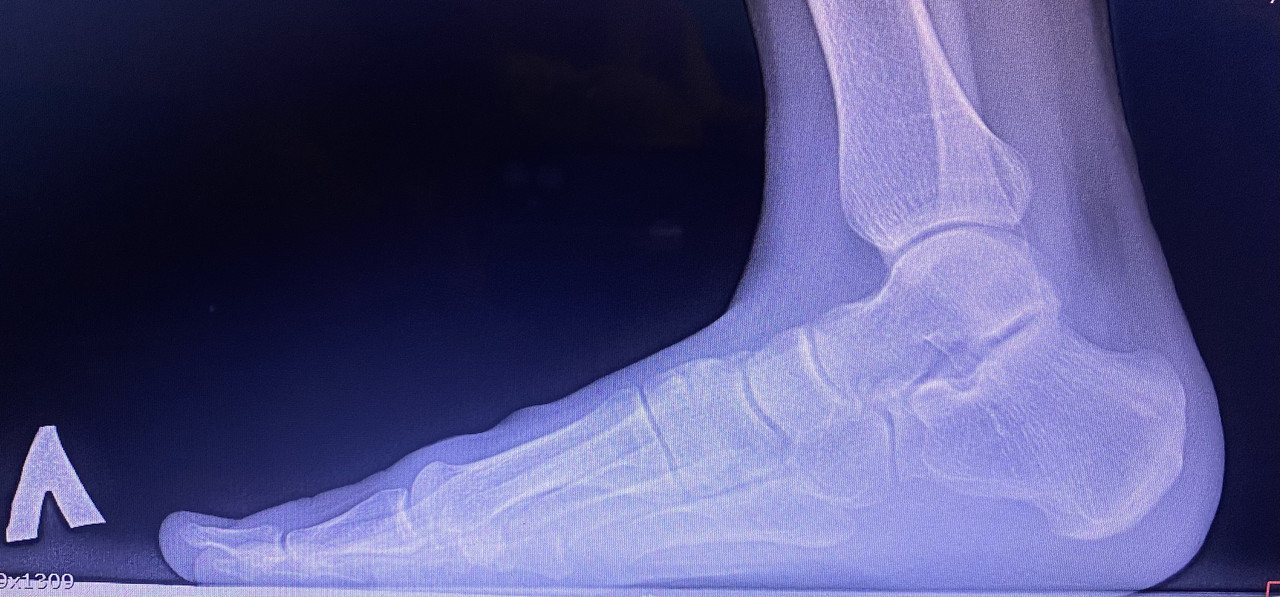

Здравствуйте, я сделал рентген стоп с нагрузкой, для определения степени продольной плоскостопии, по направлению от военкомата. В заключении написано, что на правой ноге у меня 3ст плоскостопии 158 градусов. Во время снимка я сгибал ногу в колене, поскольку это позволяет мне создать большую нагрузку для стопы. В интернете я слышал информацию, что подобные снимки военкомат считает выполненными неправильными, так ли это на самом деле?

Фото снимков приложил. spacer.png

При правильной укладке стопы для боковой проекции должна быть видна вся стопа с примерно 2 см дистального отдела малоберцовой и большеберцовой костей. Бедренная кость должна быть перпендикулярна к плоскости опоры. Дистальный отдел малоберцовой кости должен быть виден через заднюю сторону (половину) большеберцовой кости, а подошвенные поверхности головок плюсневых костей должны накладываться друг на друга при отсутствии ротации ступни.

У Вас на снимке укладка не корректная, поэтому в военном комиссариате могут направить на повторное исследование.